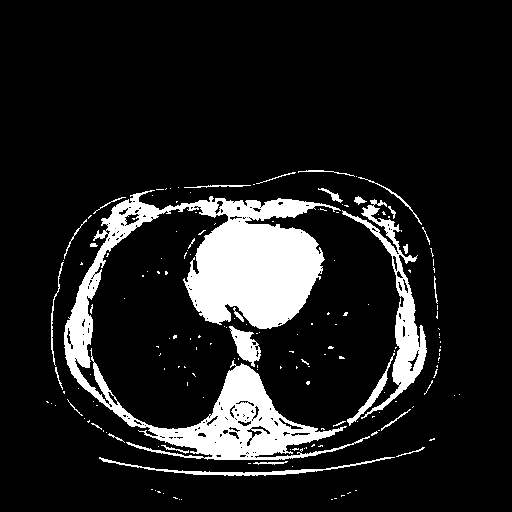

Generated VENOUS CT scan (A→B translation)

Full window (WL 1023.5, WW 4095 β†’ Low βˆ’1024, High +3071)

Actual HU range: [-1024.0, 3071.0]